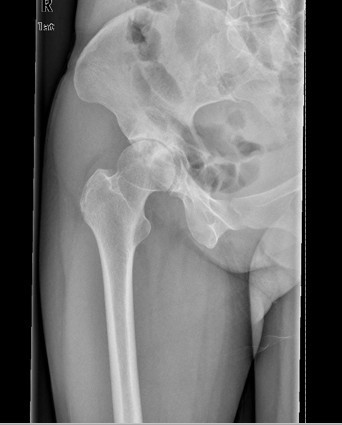

查体:右髋部软组织未见肿胀,双下肢皮肤无破溃,双足趾间皮肤干燥、完好。右髋部后侧轻压痛,双侧足背动脉和胫后动脉搏动正常。 辅查:X线:双侧侧髋臼较浅,髋臼外上方软骨下骨硬化及骨赘,Sharp角右侧约48°、左侧约50°,CE角右侧约20°、左侧约18°,右侧髋关节间隙狭窄,右侧髋臼、股骨头可见囊性改变。

诊断: 1.右侧髋关节发育不良骨关节炎(crowe I型) 2.左侧髋关节发育不良(crowe I型) 3.上呼吸道感染 治疗:排除手术禁忌症后择期手术治疗。